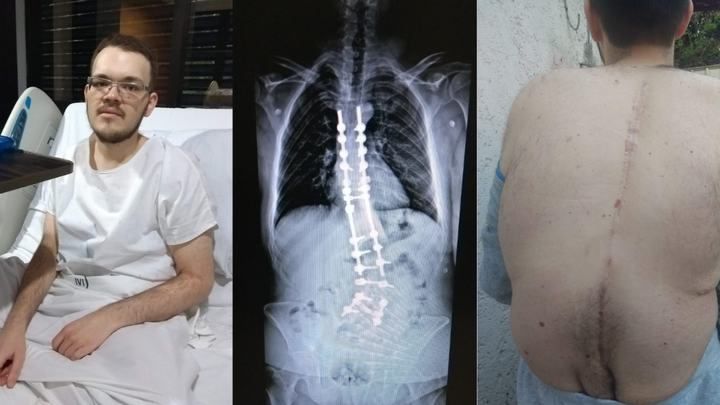

Christopher nació con escoliosis congénita, una malformación en la columna que desde la adolescencia le provoca dolor crónico e incapacitante. A los 14 años fue sometido a una cirugía en la que le colocaron barras de titanio para enderezar su columna. Aunque la operación parecía exitosa, el dolor nunca desapareció debido a daño nervioso y a su proceso de crecimiento.

Christopher was born with congenital scoliosis, a spinal malformation that has caused him severe, chronic pain since adolescence. At 14, he underwent surgery in which titanium rods were implanted to straighten his spine. Although the surgery appeared successful, the pain never subsided due to nerve damage and continued growth.